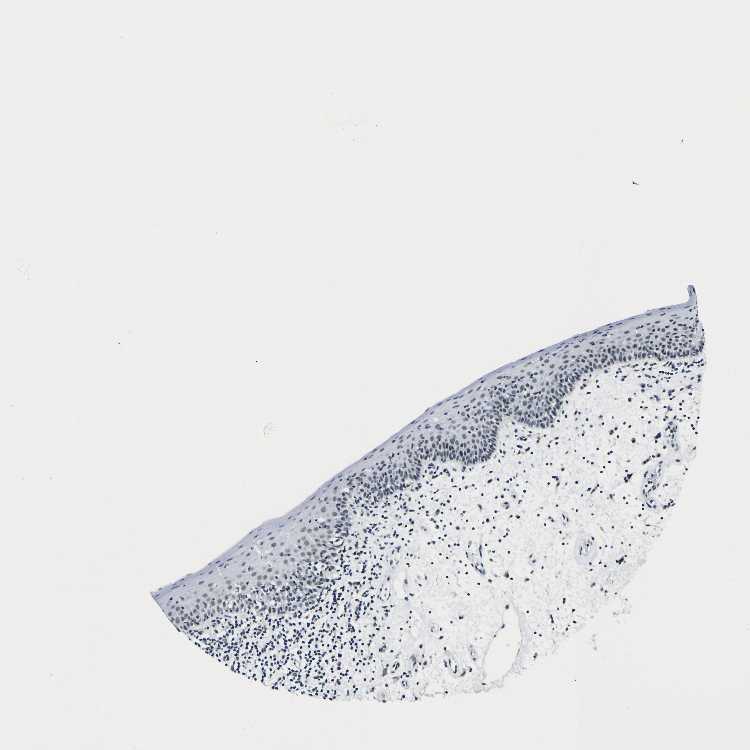

TISSUE PRIMARY DATA ORAL MUCOSA Show tissue menu

ORAL MUCOSA - Antibody stainingi

Antibody staining in the annotated cell types in the current human tissue is reported as not detected, low, medium, or high, based on conventional immunohistochemistry profiling in selected tissues. This score is based on the combination of the staining intensity and fraction of stained cells.

Each image is clickable and will lead to virtual microscopy that enables deeper exploration of all samples and also displays staining intensity scores, fraction scores and subcellular localization as well as patient and tissue information for each sample.

Antibody HPA001853Antibody HPA012292Antibody CAB000330

Squamous epithelial cells MediumLowLow